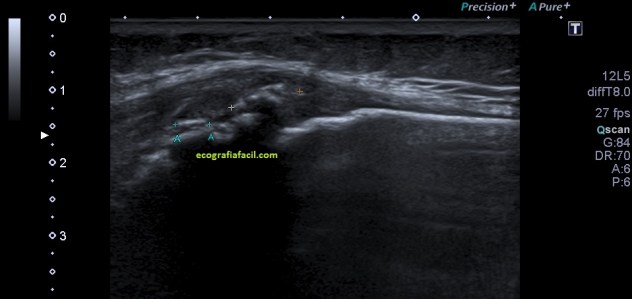

La exploración es típica para el tendón rotuliano, te enlazo la exploración para que tengas base. Cuando el paciente empieza a contar la zona de dolor, el tipo de dolor que padece y colocamos el transductor en la zona de interés, observamos esto en el corte longitudinal a la altura de la inserción del rotuliano en la tibia.

En la inserción del rotuliano, en la cara anterior de la tibia, en la espina anterior, observamos como el hueso está llamativamente irregular, parece que el tendón pudiera estar tendinopático, porque está aumentado de tamaño y además hipoecogénico. coincide con la zona de dolor. En ocasiones, cuando las metáfisis no están osificadas por completo, en adolescentes, por ejemplo, podemos ver cambios en esa zona, pero precisamente estos signos ecográficos, que se pueden dar de forma bilateral, han de ser estudiados.